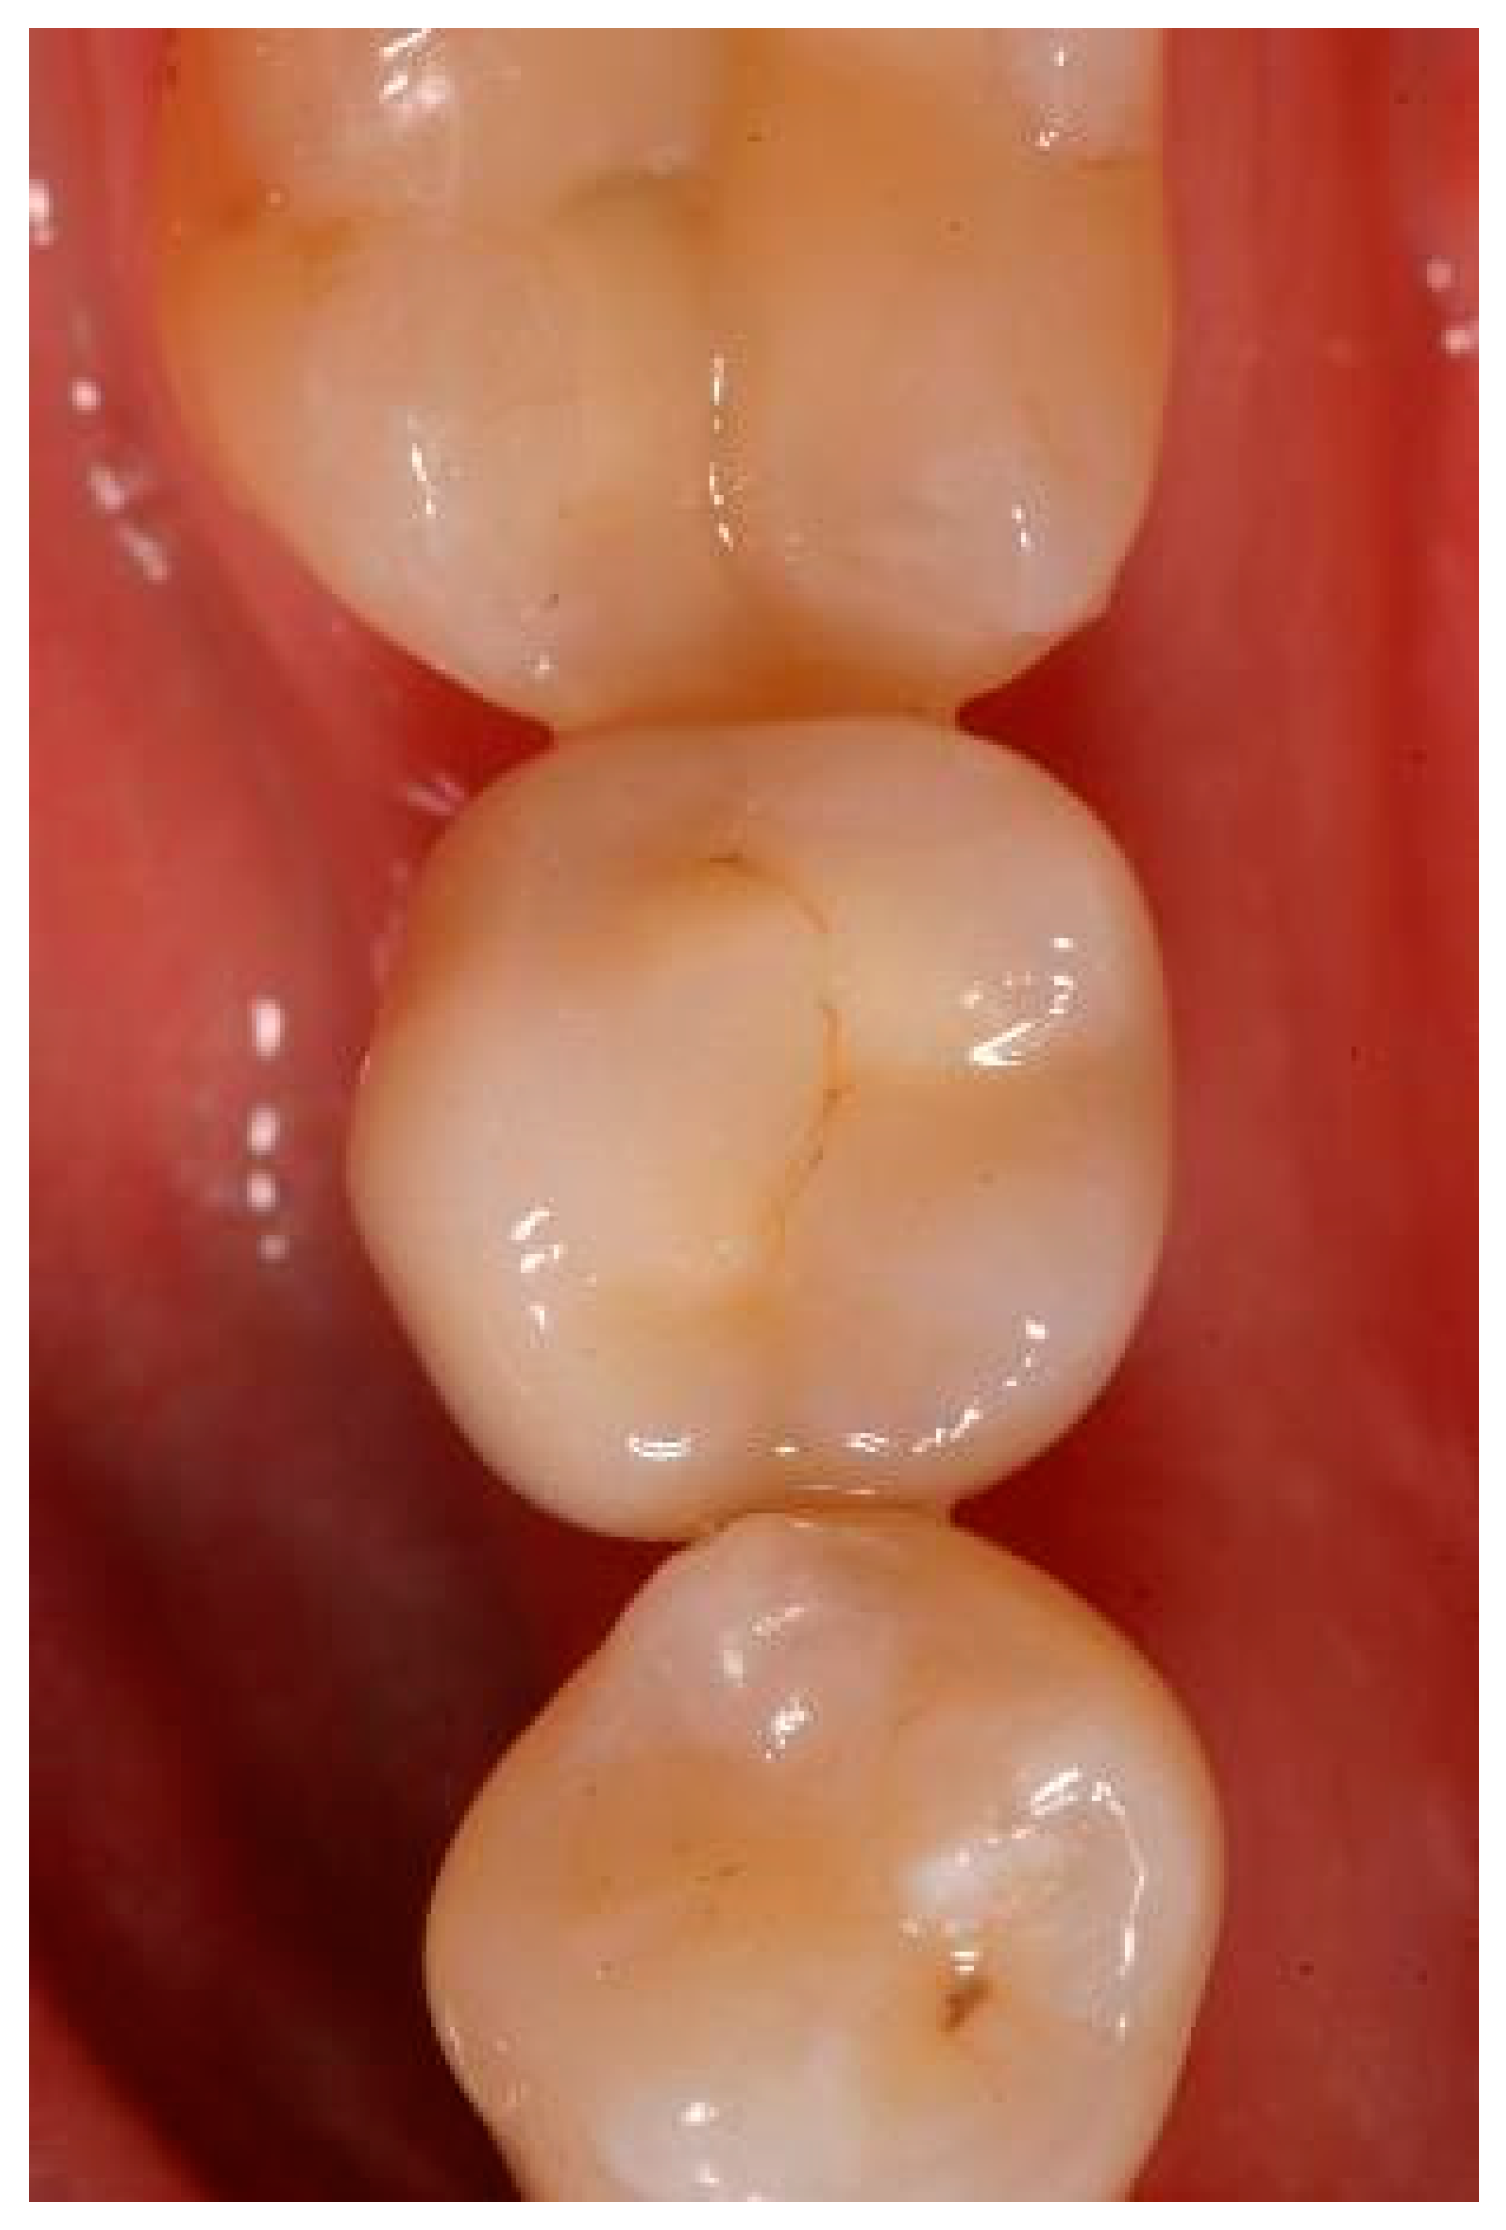

Situation after crwon cementation. Occlusal view.

Clinical situation at the 1-year follow-up. Occlusal view.

Clinical situation at the 3-year follow-up. Occlusal view.

Clinical situation at the 5-year follow-up. Occlusal view.